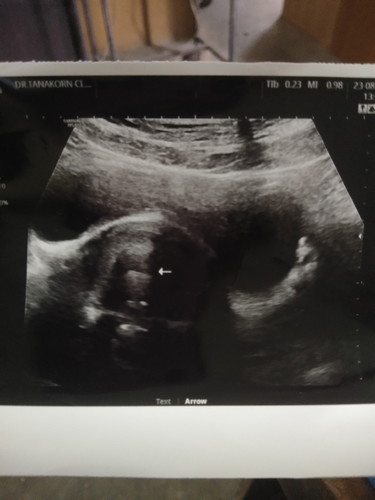

พอดีไปซาวน์มา หมอบอกไม่เจอลูกอ่ะคะ อาจจะเพิ่งเริ่มหรือท้องนอกมดลูกคะ กังวลมากว่าจะท้องนอกมดลูก มีแม่คนไหนยังซาวน์ไม่เจอลูกบ้างไหมคะ

ซาวด์ทางหน้าท้องหรือช่องคลอดคะแม่ ถ้าทางหน้าท้อง ถ้าตัวอ่อนยังเล็กมากๆ หรือเป็นคนหน้าท้องหนา อาจจะยังไม่เห็นค่ะแม่ ทางช่องคลอดจะพอมีลุ้นมากกว่าค่ะ ทั้งนี้เป็นไปได้ว่า อายุครรภ์อาจจะน้อยกว่าที่นับ เพราะไข่อาจจะตกช้ากว่ากำหนด ตัวอ่อนยังเล็กมากอยู่ จึงยังไม่พบ ก็เป็นได้ค่ะแม่ ทานโฟลิคทุกวัน พักผ่อนเยอะๆ นะคะ ซาวด์ครั้งหน้าอาจจะได้เจอกันแล้วจ้าาา